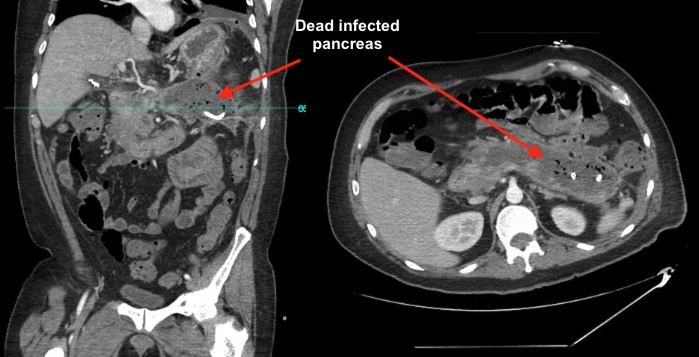

As liver, pancreas and biliary surgery push into new frontiers, so does the technology needed to plan these complex procedures. Whether laparoscopic or open surgery, every possible detail of the patient's care is analyzed to ensure surgery is safe and effective. 3D reconstructed imaging is used to plan surgery. No aspect of patient care is taken for granted.